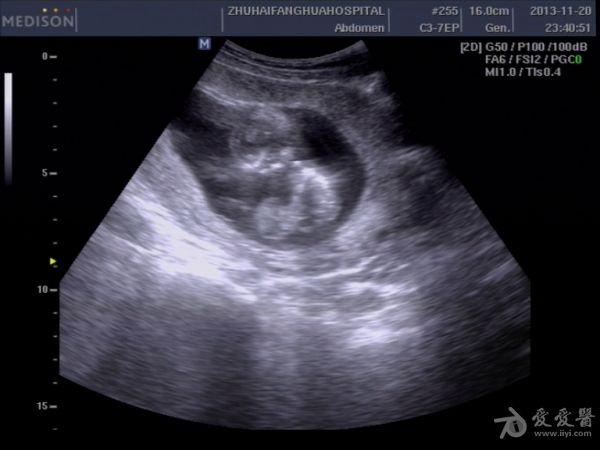

13周孕,24岁,初孕 因腹痛急诊***检查,是当天早上3点钟,医生提的黑白超,学生胆挺大的,超声图像如下:

学生直接诊断胎儿内脏外翻,上班后复查图像觉得问题不大,但还是被学生的胆大吓了一跳。这孩子连孕妇的联系方式都没留,人就放走了,今天终于联系上了孕妇,结果在市产院做的引产,结果同上。学生对我说,本来想诊断脐膨出的,觉得不像,还是像内脏外翻多些,大家说说,这孩子是该批评呢,还是该鼓励。我都有点哭笑不得了。